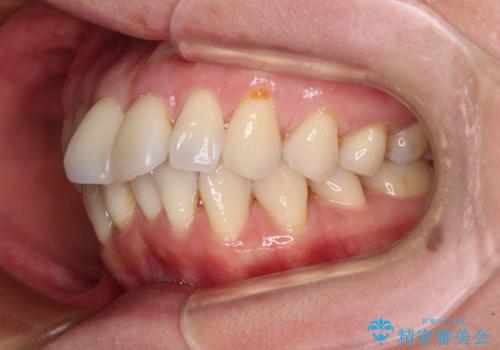

当初目論見通り、左右奥歯の咬み合わせはしっかりとさせることができました。

下唇に跡がつくほど飛び出していた上顎前歯も引っ込み、満足のいく仕上がりとなりました。